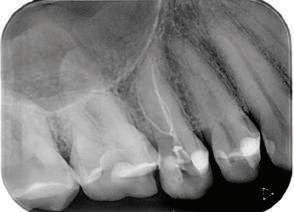

7Dental Tribune Bulgarian Edition / октомври 2022 г. Преди лечението Фиг. 1 Фиг. 4 Фиг. 7 Фиг. 10 Фиг. 13 Фиг. 16 Фиг. 17 Фиг. 18 Фиг. 19 Фиг. 20 Фиг. 11 Фиг. 14 Фиг. 12 Фиг. 15 Фиг. 8 Фиг. 9 Фиг. 5 Фиг. 6 Фиг. 2 Фиг. 3

8 Dental Tribune Bulgarian Edition / октомври 2022 г. По време на лечението Фиг. 21 Фиг. 25 Фиг. 30 Фиг. 31 Фиг. 34 Фиг. 38 Фиг. 40 Фиг. 44 Фиг. 48 Фиг. 50 Фиг. 49 Фиг. 46 Фиг. 39 Фиг. 41 Фиг. 45 Фиг. 47 Фиг. 42 Фиг. 43 Фиг. 35 Фиг. 36 Фиг. 37 Фиг. 32 Фиг. 33 Фиг. 26 Фиг. 28 Фиг. 29 Фиг. 27 Фиг. 22 Фиг. 23 Фиг. 24